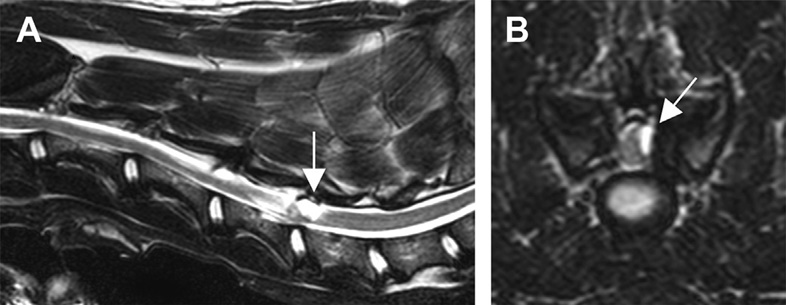

Τα κλινικά συμπτώματα είναι ανάλογα με την εντόπιση της αποφυσιακής κύστης. Η διάγνωση γίνεται με MRI, στην οποία απεικονίζονται ως καλώς περιγεγραμμένες εξωσκληρίδιες κύστεις σε μια ή σε αμφότερες τις πλευρές του σπονδυλικού σωλήνα πλησίον των αποφυσιακών αρθρώσεων. Οι αποφυσιακές κύστεις έχουν σήμα υψηλής έντασης στην ακολουθία Τ2 και σήμα ποικίλης έντασης στην ακολουθία Τ1.

Εξωσκληρίδια κύστη αποφυσιακής άρθρωσης μεταξύ Α5-Α6. Α. Οβελιαία τομή του ΝΜ Β. Εγκάρσια τομή του ΝΜ.